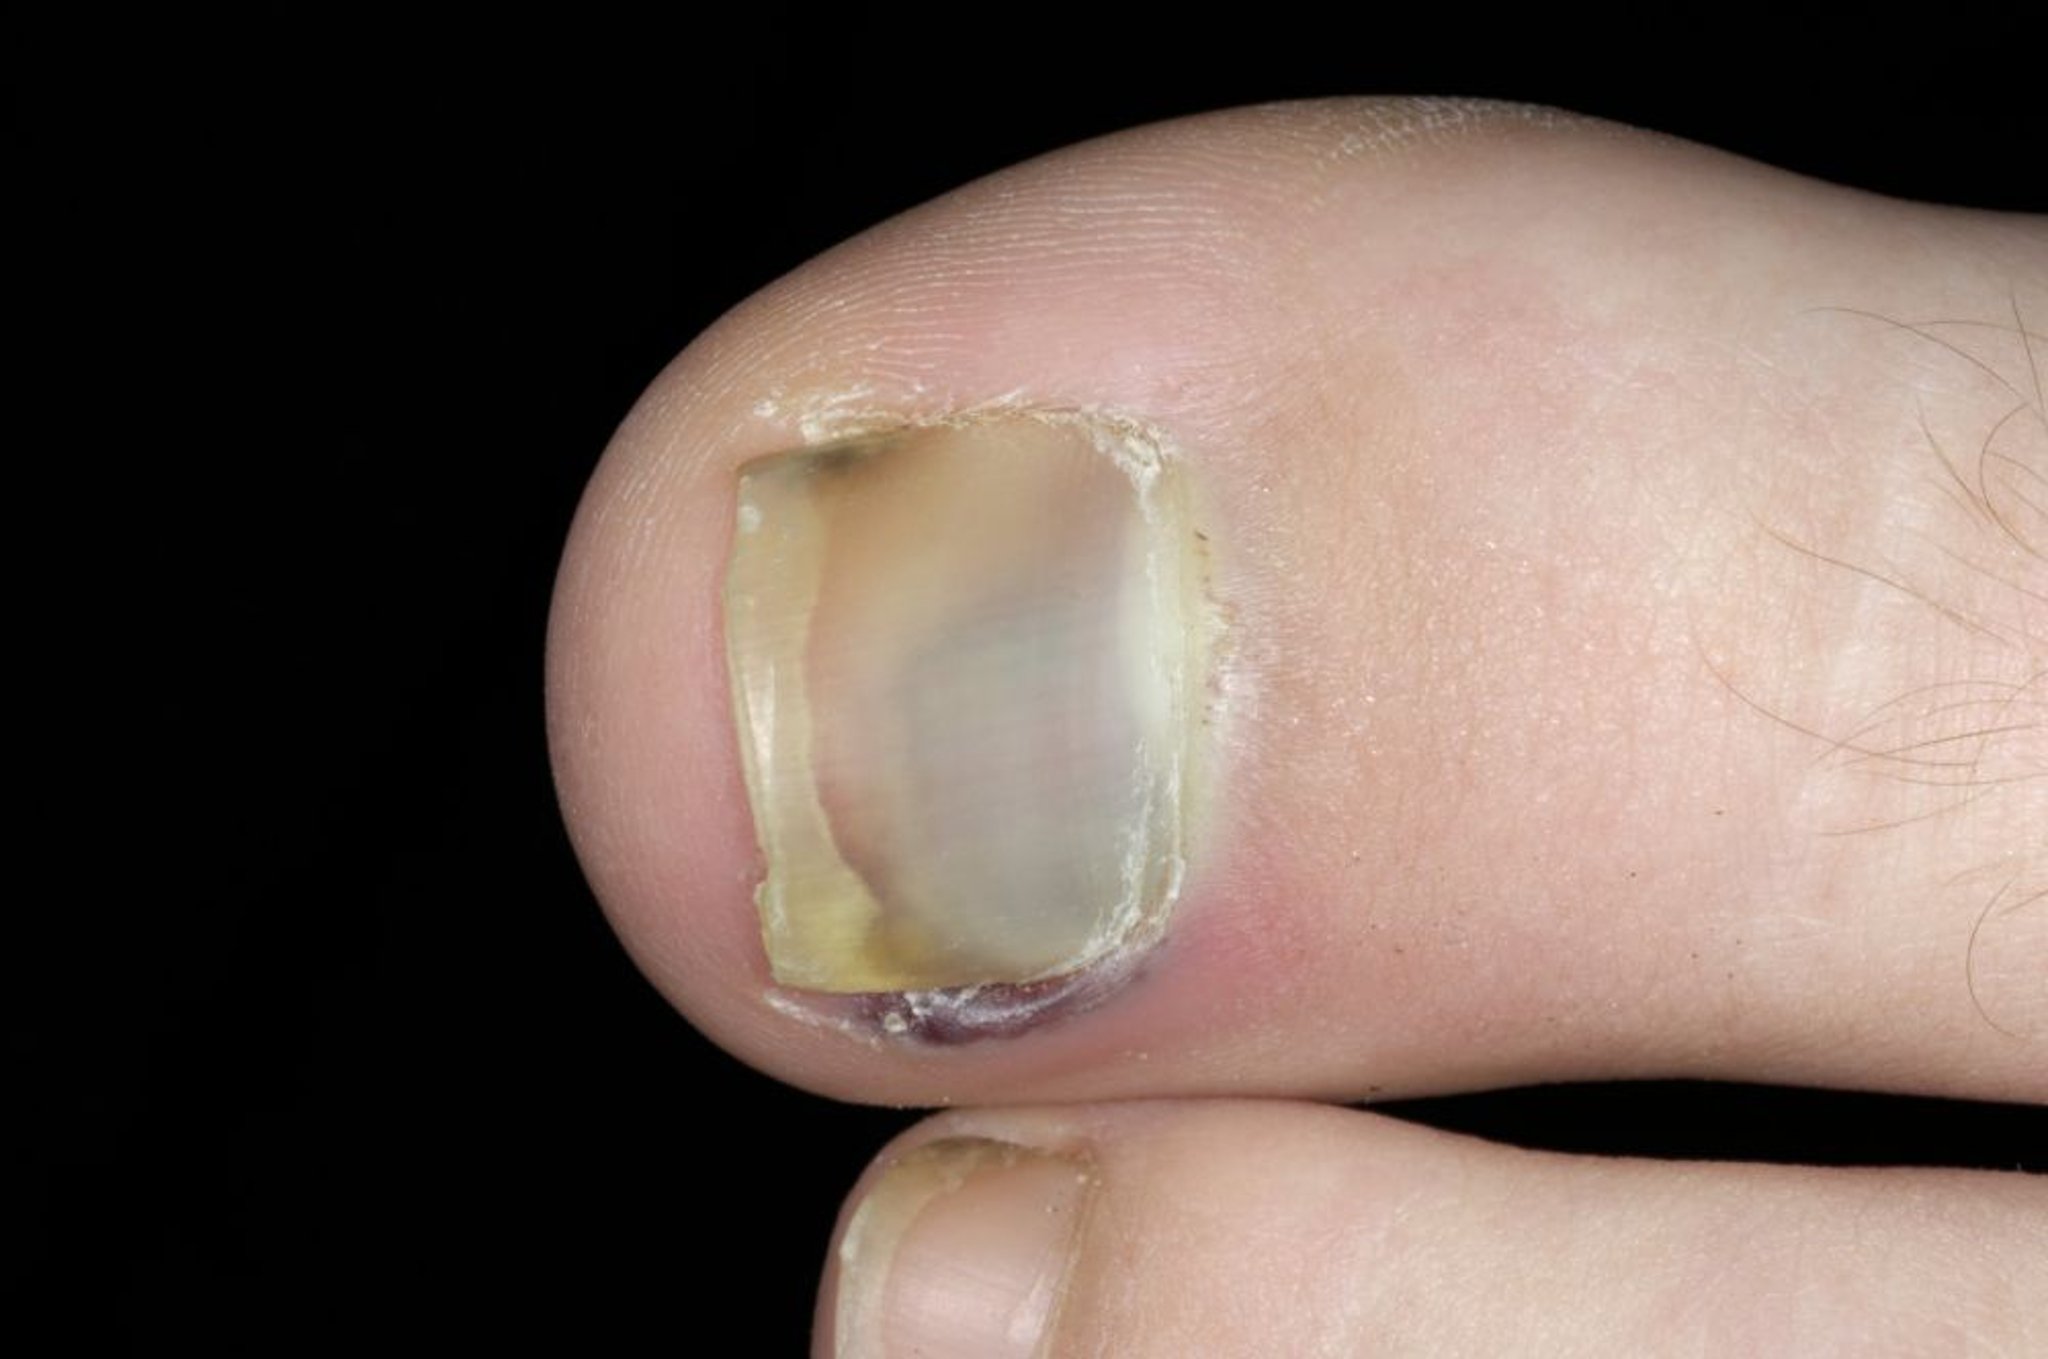

Subunguales Hämatom (Zehennagel)

Auf diesem Foto ist Blut unter dem Zehennagel vom großen Zeh zu sehen.